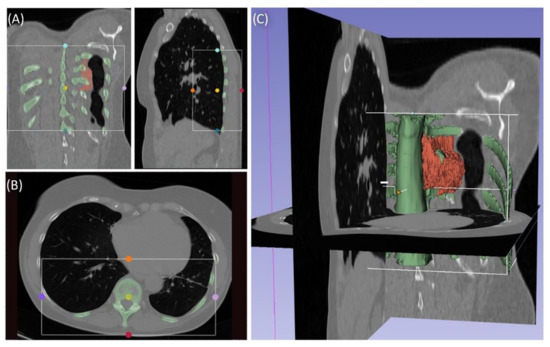

Case 3 involved a 63-year-old female patient with a diagnosed inner thoracic chondrosarcoma (G2) of the 9th left rib. The soft tissue component extended from the 7th to the 11th rib next to the aorta and lungs (Figure 5). After CT-MRI fusion and planning, marginal resection was possible by combining a partial corpectomy T7–T11 with laminectomy T7–T11 and partial resection of ribs 7–11 on the left side. Reconstruction was carried out by instrumentation spondylodesis with a screw-rod system from T5-T11 and extensive coverage with bovine pericardium (Baxter, Deerfield, IL USA) (Figure 6). The postoperative histopathological examinations confirmed tumor-free resection margins and revealed a high-grade tumor (G3). After adjuvant radiation and a four-month postoperative follow-up, there was no sign of local recurrence. The patient returned to daily life without any sensomotoric deficit.

Figure 5. Segmentation of a thoracic chondrosarcoma and preparation for 3D model printing; cross-sectional segmentation (A,B) and 3D model with tumor volume (red) (C).